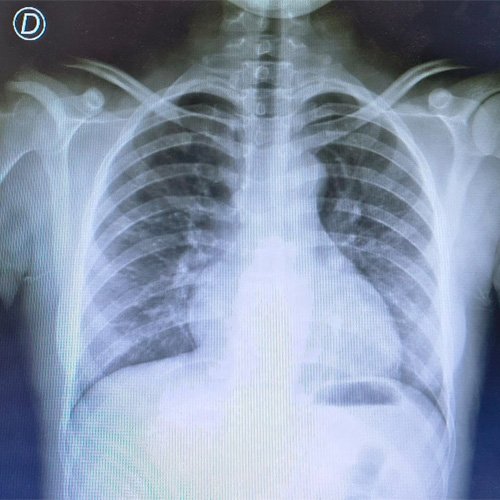

• Radiografía de tórax frente/perfil (Día 0): rotada, índice cardiotorácico impresiona conservado , senos costofrénicos libres, no se visualiza condensación pleuroparenquimatosa.

Anexo Día 0: radiografia de torax